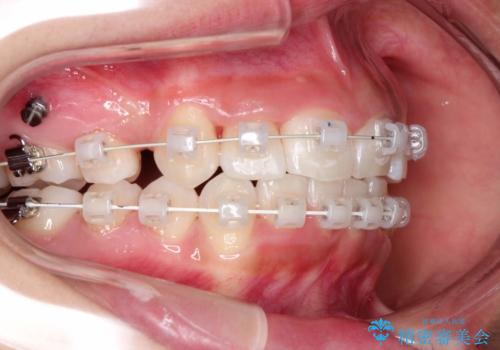

- 前歯のがたつきと出っ歯が気になるとのことで来院されました。

上顎の前から4番目の歯を両側合計2本抜歯して矯正することとなりました。

抜歯をして矯正をすることで、前歯を後方に移動させ、ガタガタを改善することができました。